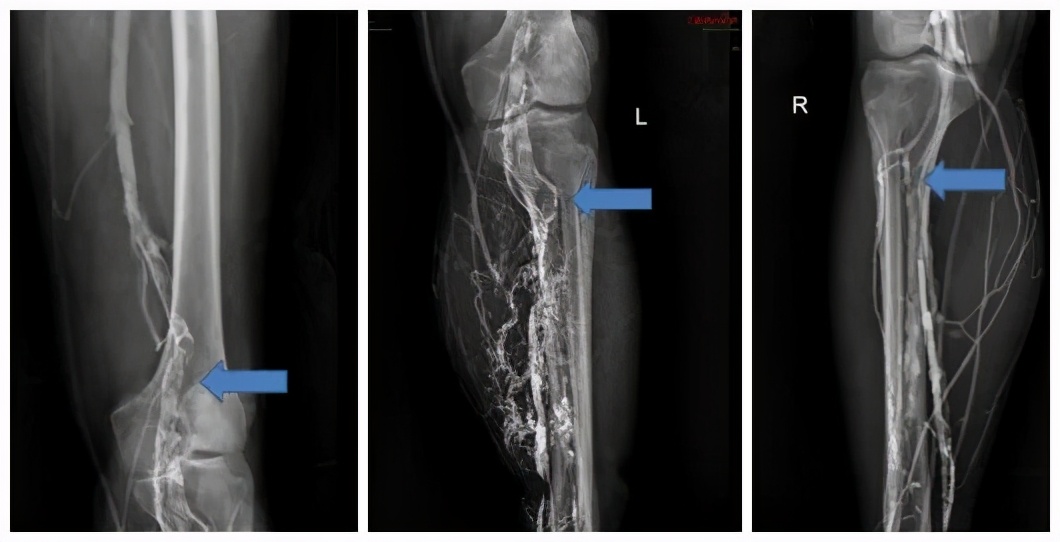

患者双下肢深静脉形成大面积血栓,介入科林明强主任及于大威主治医师讨论后认为此患者一方面需尽早手术,另一方面需要避免血栓脱落造成生命危险,遂立即为患者行下腔静脉可转换腔静脉滤器置入。

静脉造影